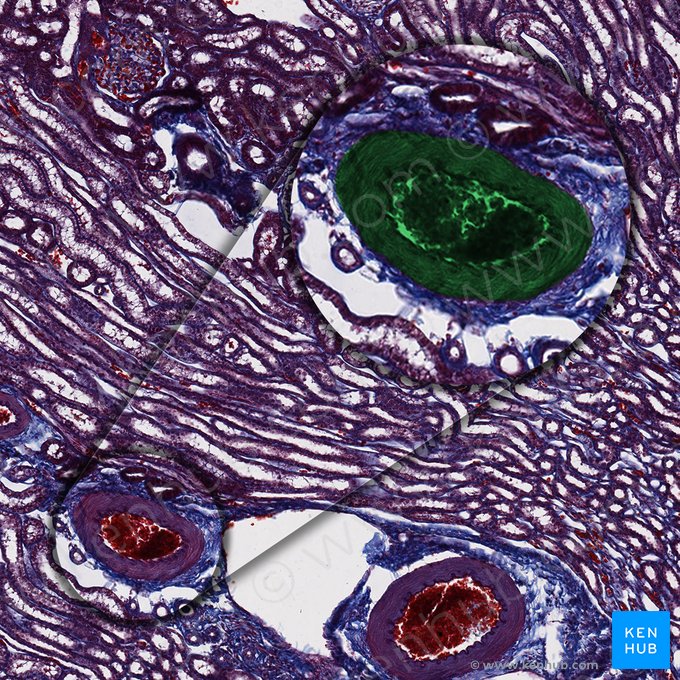

Die Nieren sind paarige retroperitoneale Organe des Harnsystems, die das Blut filtrieren, Urin produzieren, Hormone synthetisieren und den Elektrolyt- und Säure-Basen-Haushalt kontrollieren. Jede Niere besteht aus einer Rinde, dem Mark und dem Nierenbecken

• Die Nierenrinde ist die äußere Schicht des Nierengewebes und enthält die gewundeneen Anteile der Nephrone (Nierenkörperchen und Tubulus convolutus).

• Das Nierenmark besteht aus Pyramiden, die durch die Säulen voneinander getrennt sind. Die Spitzen der Pyramiden ragen in Richtung Nierenbecken und münden über die Area cribosa in die kleinen Nierenkelche. Jede Nierenpyramide bildet zusammen mit dem sie umgebenden Gewebe einen Nierenlappen. Die Nierenlappen werden weiter in Nierenläppchen unterteilt. Jedes Läppchen besteht aus einer Gruppe von Nephronen, die in ein Sammelrohr münden.

• Das Nierenbecken besteht aus den kleinen und großen Nierenkelchen, die mit Übergangsepithel (Urothel) ausgekleidet sind und von einer Lamina propria sowie glatten Muskelschichten gestützt werden. Dieses System sammelt den Urin von den Nierenpapillen und erleichtert dessen Weiterleitung in den Harnleiter.